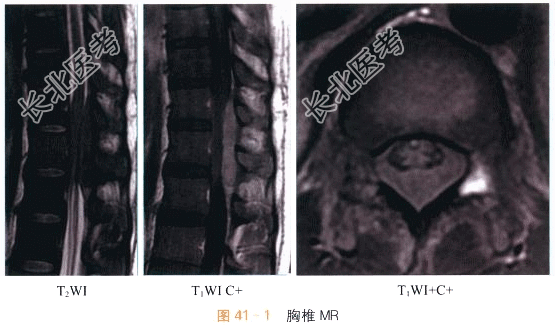

读片分析:胸椎矢状面、横轴位MR成像示T7~8水平椎管内硬膜外占位性病变,T2加权像上,病变信号等于脊髓,病变梭形纵向生长,沿硬膜外间隙包绕挤压脊髓,病变侧蛛网膜下腔变窄;增强后MRI显示病变呈明显均匀强化。